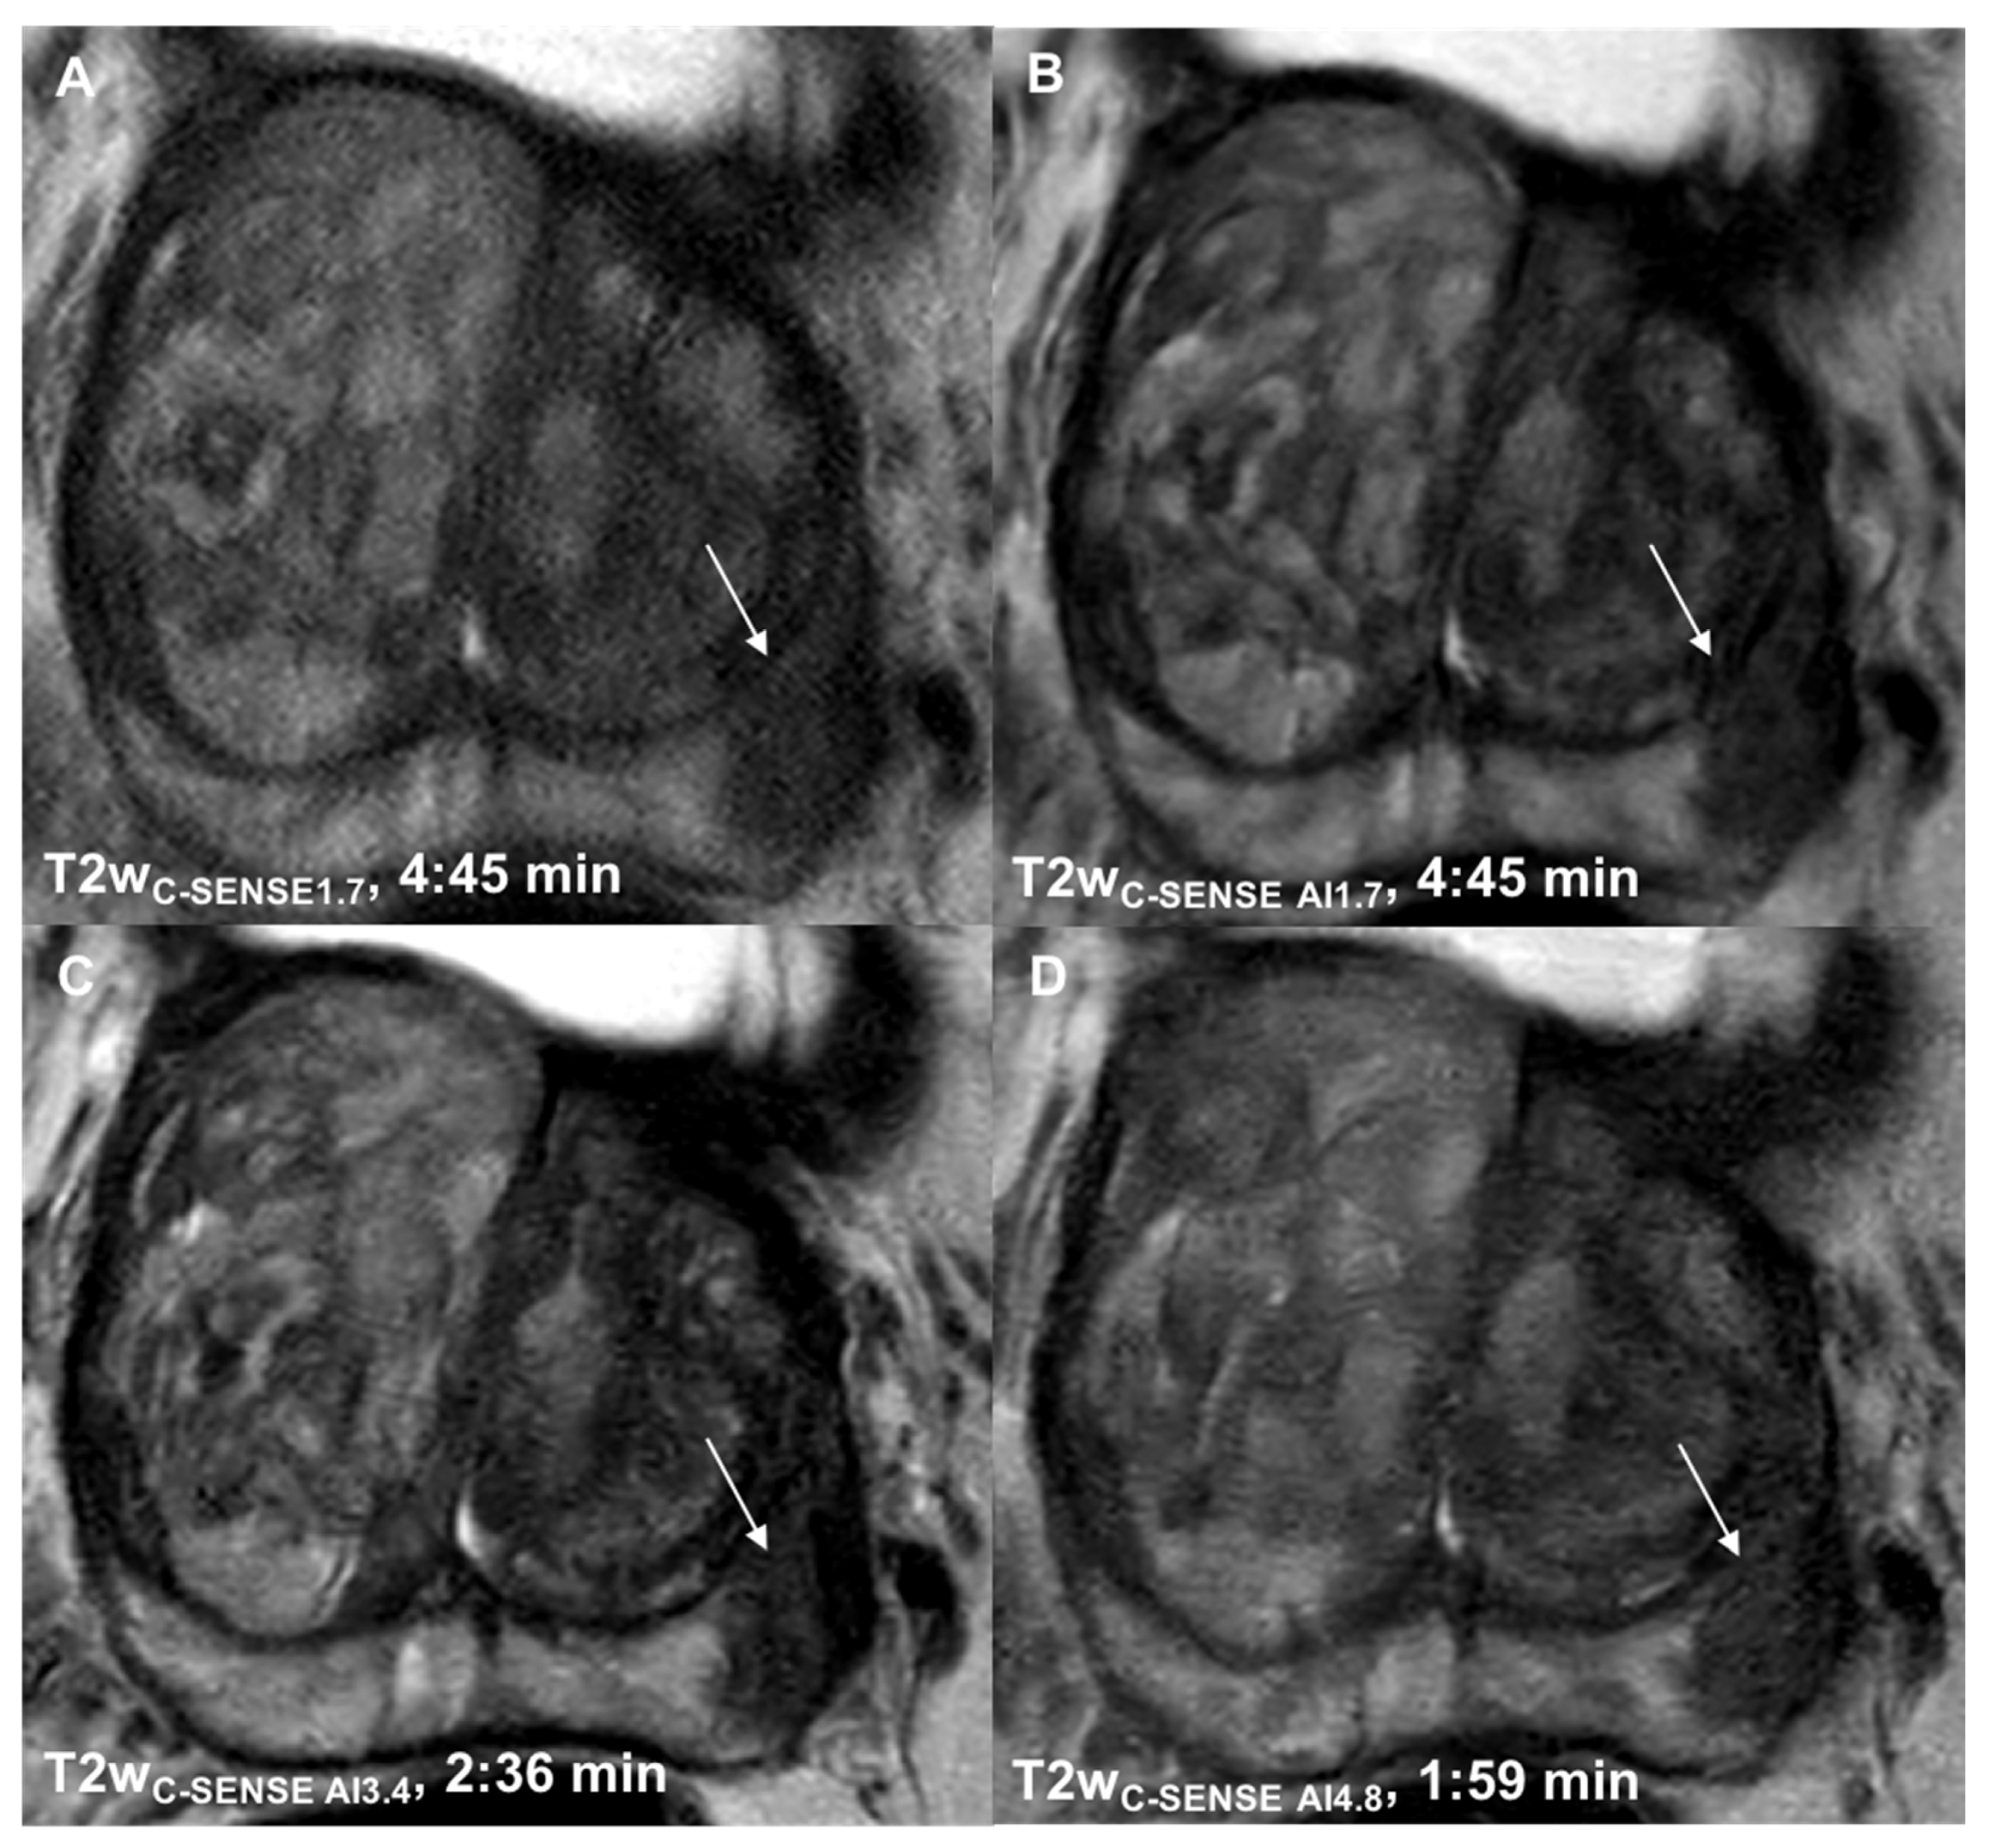

3.1. Determination of Suitable Acceleration Factors

3.2. Qualitative Analysis

3.2.1. Image Quality

3.2.2. Noise

3.2.3. Motion Artifacts

3.2.4. Image Sharpness

3.2.5. Lesion Detection and Diagnostic Certainty

3.2.6. T2 and PI-RADS Scores

| Scan time (min) | 4:45/2:36/1:59 | 5:12 (b50-1000) 3:48 (b1500) |